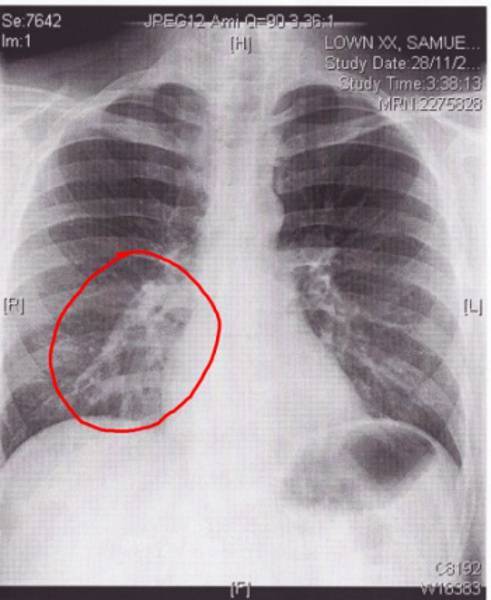

Оптимальным способом дифференциации обструктивного бронхита от воспаления легких является рентгенография. Зачастую ее вполне достаточно, и не приходится прибегать к дополнительной лабораторной диагностике. Если же на рентгеновском снимке картина заболевания недостаточно ясна, назначается бронхоскопия, МРТ и другие исследования.

Еще проводят рентгенографию – обычно на снимке ясно различаются признаки воспалительного процесса, характерного для пневмонии.

При бронхите на снимке контур бронхиального дерева становится более чётким, усиление лёгочного рисунка свидетельствует о наличии воспалительного процесса.

При обследовании лечащий врач обнаруживает хрипы в бронхах. Они могут определяться с одной стороны или иметь двусторонний характер. При подозрении на острый бронхит, и также воспаление легких, врач назначает дополнительное обследование-рентген. На снимке бронхит выглядит как «усиление легочного рисунка». Бронхиальное дерево лучше просматривается и определятся.

Опытный врач знает, как отличить острый бронхит от пневмонии. При прослушивании врач наблюдает изменения в виде хрипов и прослушиваются они локально, в зоне воспаления. Хрипы при бронхите отличаются равномерным расположением. При подозрении на пневмонию врач назначает рентгеновское обследование. На снимке воспаление легких видно, как затемненные участки с четкими границами. Пневмония может поражать от 1/3 до 2/3 всего легкого.

Как отличить бронхит от пневмонии по результатам рентгеновского снимка

Несмотря на некоторые различия пневмонии и бронхита, нередко клиника бывает размытой. В такой ситуации для установления верного диагноза необходимо сделать флюорографию или рентгенографию – это наиболее достоверный способ диагностики. По результатам рентгенограммы лечащий врач сможет легко распознать болезнь. Худшие опасения подтвердятся, если на снимке будут отчётливые затемнения.

| Рентгенографическая картина | инфильтрат (как правило, в нижней доли легкого), расширение корней | усиление легочного рисунка |